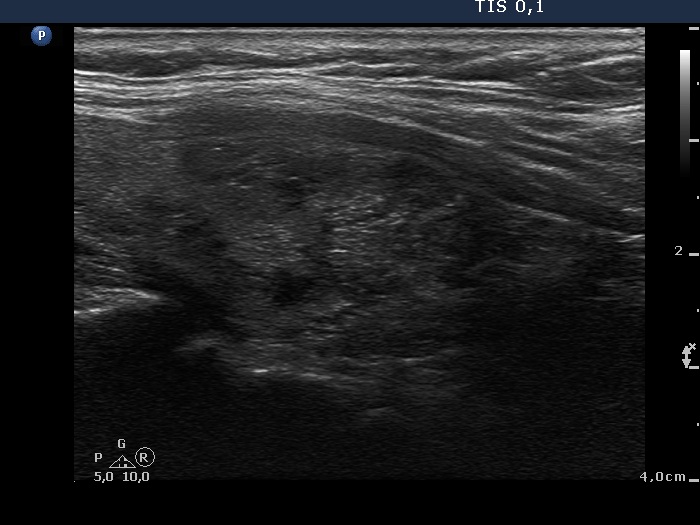

Hashimoto's thyroiditis without any nodule (histological diagnosis) - case 1520 |

The coexistence of tiny punctate granules and similarly bright lines is the hallmark of connective tissue. There is a brighter and relatively large granule in the ventral small lesion in the upper image which might be either a punctate echogenic focus or a sign of fibrotic changes.